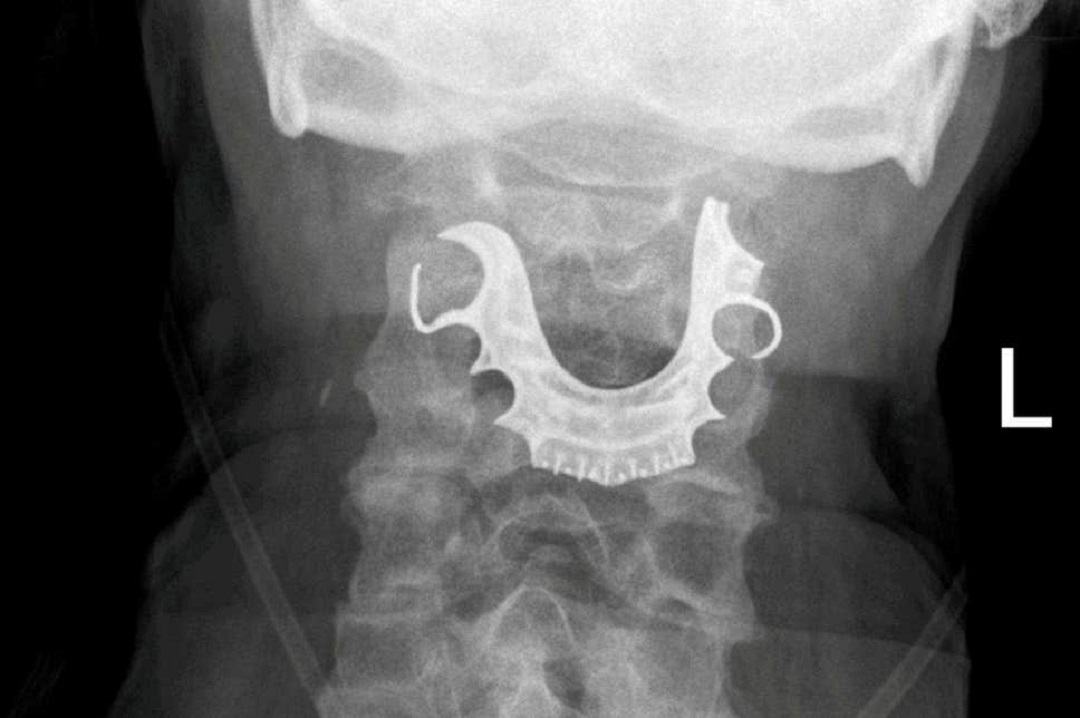

Bajo el nombre de ElectRx, el proyecto –que bien podría llamarse Arma X– tiene como objetivo explorar la neuromodulación de funciones de órganos para ayudar al cuerpo humano a curarse por sí mismo de lesiones graves de una forma rápida y eficaz. El secreto detrás de este nuevo “factor de curación avanzado” se encuentra en crear el equivalente a un “sistema de circuito cerrado” en el cuerpo de los soldados, quienes tendrán una especie de “marcapasos inteligente” dentro de su cuerpo, el cual les proporcionará diferentes estímulos de curación sin la necesidad de tener que usar medicamentos.

En la explicación del proyecto proporcionada por la DARPA, se afirma que el sistema nervioso periférico del cuerpo se encarga de monitorear el estado de los órganos internos y ayuda a regular la respuesta biológica a las infecciones, lesiones u otros desequilibrios. A través de implantes en el cuerpo, DARPA busca tomar control del sistema nervioso periférico y regular desde éste la salud de sus soldados, gestionando de manera más eficaz la modulación precisa del sistema nervioso periférico.

La tecnología del proyecto ElectRx, compuesta de biosensores y diversos dispositivos implantados por medio de inyecciones, sería mínimamente invasiva, pero, de acuerdo con la Agencia, de dar resultados tendría un gran impacto en la salud de los soldados y, a la larga, de toda la gente en general. Según las estimaciones de DARPA, si consiguen lo que quieren con ElectRx, se podrá tratar enfermedades como la artritis o el estrés postraumático de una manera eficaz.